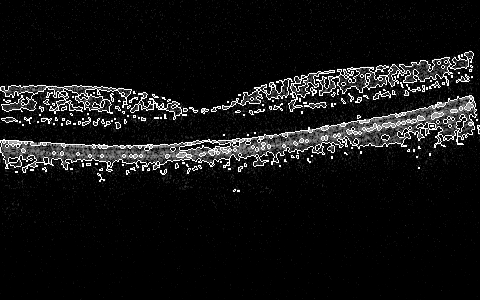

More interesting preliminary results include global 2D (2D at the moment, per slice, but will expand the window to 3D space next) processing that includes in one algorithm some subalgorithms that do preprocessing, skeletonizing, or filling/thinning, and active-contouring of the images from the Zhang-Suen transform. There are many of the options and configurable parameters to try, but already now the outlines of the ILM, IS/OS, RPE can be seen in a very draft debug mode in Figure 7, Figure 8, Figure 5, Figure 6, Figure 9, and Figure 10.

Figure 5: 2D Zhang-Suen Skeletonizing near Fovea

Refer to caption

Figure 6: 2D Zhang-Suen Skeletonizing of Slice 90

Figure 7: 2D Zhang-Suen Filling-Thinning-Contouring near Fovea

Figure 8: 2D Zhang-Suen Filling-Thinning-Contouring of Slice 90

Figure 9: 2D Zhang-Suen Filling-Thinning-Skeletonizing near Fovea

Figure 10: 2D Zhang-Suen Filling-Thinning-Skeletonizing of Slice 90